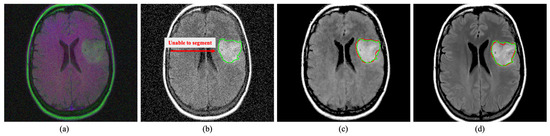

The image noise can also startlingly effect the medical image segmentation process similar to the detection methods, as shown in Figure 10. Here, segmentation has performed on brain MRIs using well-known U-Net architecture [68]. It has observed that image noise make the segmentation process substantially unsatisfactory. However, a sophisticated MID method like the proposed DRAN can assist the segmentation method by mitigating image noise.

Figure 10. Segmentation on brain MRI image. The green and red outline indicate the ground truth and the segmented area. The proposed DRAN can drastically improve the segmentation performance by excluding the noise present in the target image. (a) Noisy image. (b) Noisy image + U-Net [68]. (c) Denoised image obtained with DRAN + U-Net [68]. (d) Reference clean image + U-Net [68]. Source by: (https://www.kaggle.com/mateuszbuda/lgg-mri-segmentation).